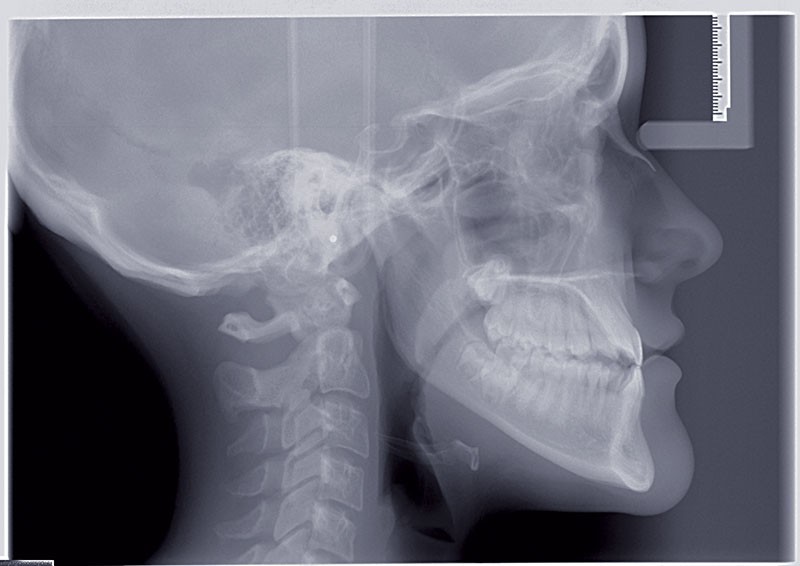

Nous sommes en présence d’une patiente en fin de croissance faciale, âgée de 16 ans. Elle présente une classe III dentaire et squelettique associée à une asymétrie faciale de type latérognathie mandibulaire avec déviation des points interincisifs et déviation du menton vers la gauche.